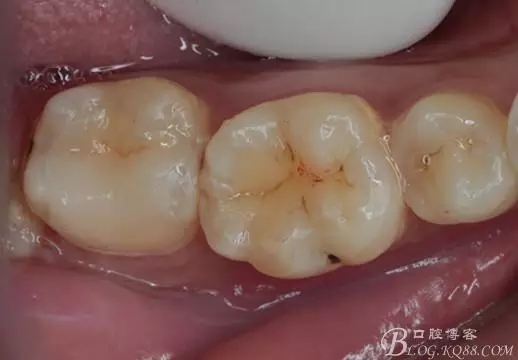

一周后復診,37臨時充填物完好。去除臨時充填物,清潔基牙,試戴嵌體,就位良好,邊緣密合。取下嵌體,常規(guī)處理,9.5%HF處理20S,沖洗一分鐘,95%酒精蕩洗5分鐘?;劳磕?7%的磷酸凝膠,釉質(zhì)區(qū)域酸蝕30S,本質(zhì)區(qū)域15S。粘固用的是3M第八代粘接劑套裝,照說明書逐步操作。最終固化時涂滿阻氧劑,每個牙面最少光照30S,光固化燈用漸強模式。常規(guī)調(diào)合,配合硅膠尖套裝拋光。術后常規(guī)醫(yī)囑,不適隨診。

④嵌體顏色與基牙的差異也是一遺憾。